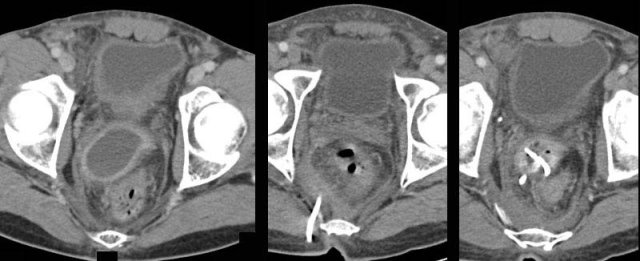

Some patients with an “appendiceal abscess” are better off with immediate surgery.

These two patients were both ill with a high CRP and signs of generalized peritonitis.

US and CT confirmed paralytic ileus and large, not-well walled-off air-fluid collections, and in the right patient some free air (arrows).

These combined clinical and CT findings indicate a failing defense mechanism, warranting surgery.

Children often present with free perforated appendicitis, because the disease progresses more rapidly and abscess formation is less effective than in adults.

Children with an appendiceal abscess usually undergo surgery.

In this 11 year old girl with a ten days old large retrocecal abscess, both drainage and appendectomy was easily performed laparoscopically.

Finally, in patients with a small (< 2 cm) abscess (*) close to the appendix (arrows) who have only 3-4 days of symptoms, immediate appendectomy with removal of the small abscess is a good option.

Note the fecolith (arrowhead)